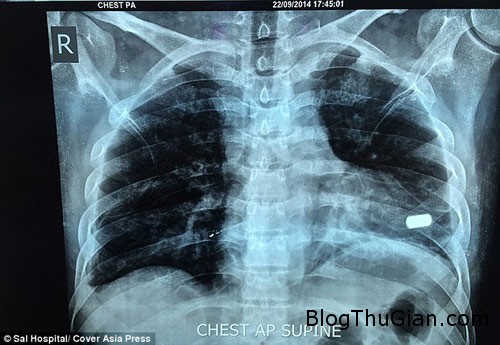

Viên đạn nằm ngang giữa đỉnh tâm thất trái

Ông Jain, bác sĩ của Bệnh viện Sal ở Ahmedabad, cho biết: “Viên đạn nằm ngang giữa đỉnh tâm thất trái. Nó chỉ nằm cách buồng tim bên trái 1mm và có thể đã giết chết Sharma. Do bệnh nhân đã từng mất rất nhiều máu nên chúng tôi phải hết sức cẩn thận”.